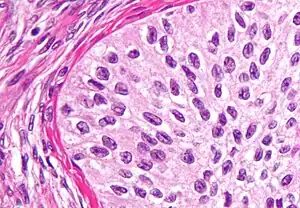

Endometrioid tumors

Endometrioid tumors account for approximately 20% of all ovarian cancers and are mostly malignant (endometroid carcinomas). They are made of tubular glands bearing a close resemblance to benign or malignant endometrium. 15-30% of endometrioid carcinomas occur in individuals with carcinoma of the endometrium, and these patients have a better prognosis. They appear similar to other surface epithelial-stromal tumors, with solid and cystic areas. 40% of these tumors are bilateral, when bilateral, metastases is often present.

Pathology

- Glands bearing a strong resemblance to endometrial-type glands

- Benign tumors have mature-appearing glands in a fibrous stroma

- Borderline tumors have a complex branching pattern without stromal invasion

- Carcinomas (malignant tumors) have invasive glands with crowded, atypical cells, frequent mitoses. With poorer differentiation, the tumor becomes more solid.